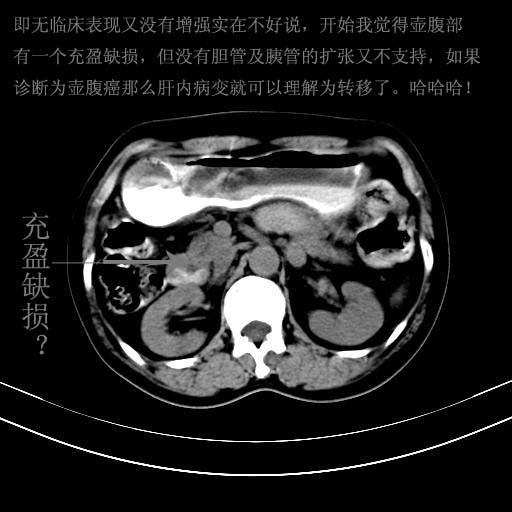

胃内见充盈缺损,建议行胃镜病理检查,如果胃内无占位,则肝内考虑左叶、尾叶为包膜型肝癌,如有则考虑为转移瘤

胃内的充盈缺损,当时让患者俯卧位在扫描一下就 好了,当然最好是增强扫描,肝脏的病灶平扫很难定性,可以考虑是肝癌·血管瘤·转移瘤!

胃内的充盈缺损因胃壁不厚,我个人考虑为胃内残留物。肝左叶及尾叶病灶,我首先考虑血管瘤,其次为肝癌。(尾叶的更低密度区太规整)

胃内见充盈缺损,最好查胃镜

胃内见充盈缺损,建议胃透或胃镜检查。

胃内的充盈缺损,当时让患者俯卧位在扫描一下就好了,增强扫描,肝脏的病灶平扫很难定性.

胃内充盈缺损考虑为胃内存留物,肝左叶和尾状叶两个病灶,均为低密度,建议增强。

胃内充盈缺损考虑为肿瘤,肝尾叶及左叶肿块考虑转移瘤

胃癌肝内转移及肾上腺转移。

胃窦部占位伴肝及左肾上腺转移可能大,建议增强扫描。